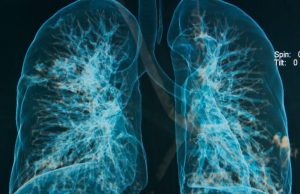

COPD patients who switched from smoking to using HTPs, showed consistent improvements in respiratory symptoms, exercise tolerance, and their general quality of life.COPD is...

Ex-Smoking COPD Patients Who Switched to Vaping Experienced Long-Term Benefits

The participants who switched to vaping reported a reduction of about 50% in flare ups, a significantly improved cardio-respiratory health, and increased exercise ability...